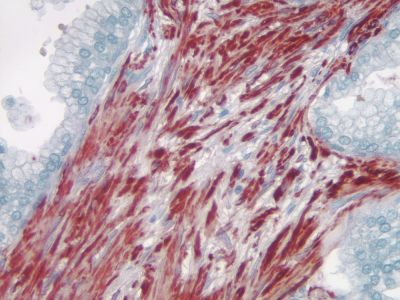

ImmPACT AMEC Red HRP Substrate utilizes Vector Laboratories ImmPACT technology to generate a crisper, brighter red reaction product that is 5 -10 times more sensitive than conventional AEC substrates and can be used as a single label or as a second color for multiple antigen labeling.

| Chromogen Color | Red |

ImmPACT AMEC Red chromogen can be used for both manual and automated staining methods. Stained slides must be aqueously mounted because the reaction product is soluble in organic solvents. Precipitated ImmPACT AMEC Red is stable for at least 2 years when mounted in VectaMount? AQ (H-5501).